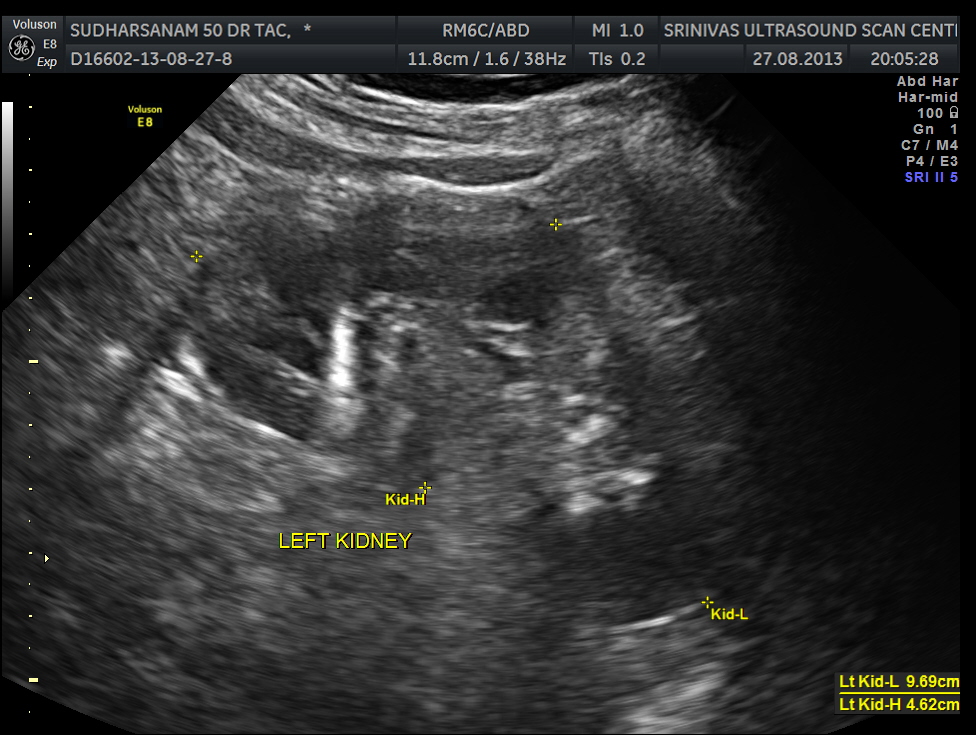

He had an essentially normal appearance of the upper abdominal organs . His kidneys also appeared to be normal.

images of the kidney are given below.